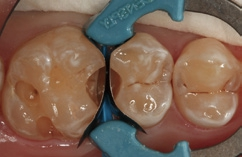

Fall 6 Minimalinvasive Behandlung von tiefen Approximalläsionen an Zähnen 14 und 15

Bei dem 26-jährigen, frisch approbierten Zahnarzt imponierte eine untypisch hohe Kariesaktivität mit etlichen, teils sehr tiefen Approximalläsionen, die einer therapeutisch- restaurativen Intervention bedurften. An den Zähnen 14 und 15 zeigte sich eine auffällige Transluzenzänderung des Zahnschmelzes, was immer ein untrügerisches Zeichen für eine darunterliegende, bereits in das Dentin penetrierte Karies darstellt (Abb. 23). Die Abbildung 24 verdeutlicht – noch während der Exkavation – das Ausmaß des vorgefundenen Defektes. In der Abbildung 25 sind die vollständigen Kavitäten, bereits mit Teilmatrizen und einem Palodent V3-Spannring isoliert, erkennbar. Durch den hervorragenden Separationsdruck dieser Art von Spannringen können benachbarte Approximalläsionen in der Regel problemlos zeitgleich versorgt Anwerden. Nach der adhäsiven Vorbehandlung – im vorliegenden Fall mit einem klassischen Mehrflaschen-Etch&Rinse- Adhäsiv (Abb. 26) – erfolgte die Versorgung mit SDR flow+ in der Farbe A3 in zwei horizontalen Inkrementen. Beide Inkremente, die eine Dicke von ca. 3 mm aufwiesen, wurden für je 40 Sekunden gemäß Herstellerangaben polymerisiert. Eine gemeinsame abschließende Polymerisation für 20 Sekunden nach Entfernen der Matrizen ergänzte das Aushärtungsprotokoll. Die Abbildung 27 zeigt die Situation direkt nach Ausarbeitung und Politur, die Abbildung 28 bei einer weiteren Nachkontrolle nach drei Monaten. Es zeigte sich nach der Rehydrierung der Strukturen eine deutlich bessere Farbadaptation als initial, unmittelbar nach dem Legen.